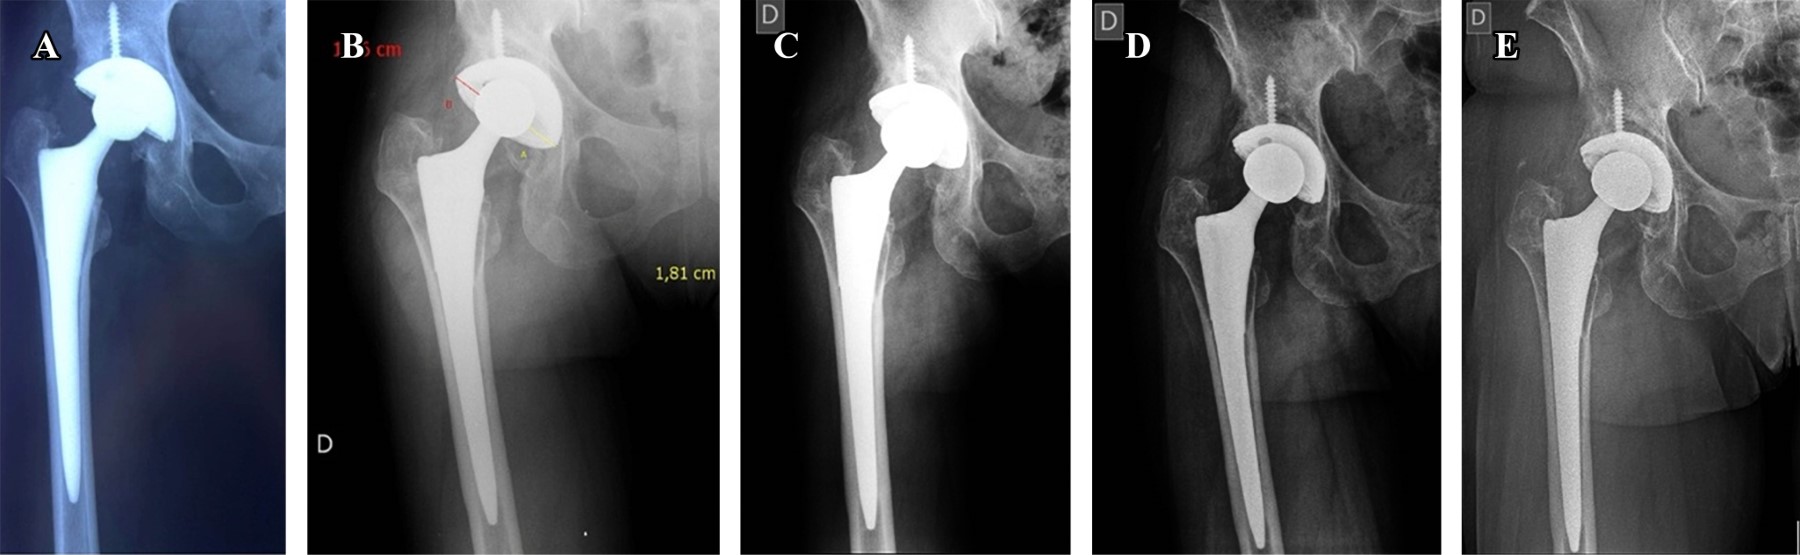

La Figura 1 muestra el análisis de supervivencia de los pacientes sometidos a artroplastía total de cadera con vástago Synergy. Para esta gráfica se consideró como evento a cualquier complicación que ameritó revisión, independientemente de la causa. A los 20 años, el número de pacientes que estuvieron en riesgo fue 18 y se presentaron un total de 13 revisiones(Figuras 2 y 3).

La Figura 4 muestra el análisis de supervivencia de los pacientes hasta la revisión por aflojamiento aséptico. A los 20 años no se presentaron eventos relacionados con el aflojamiento aséptico.